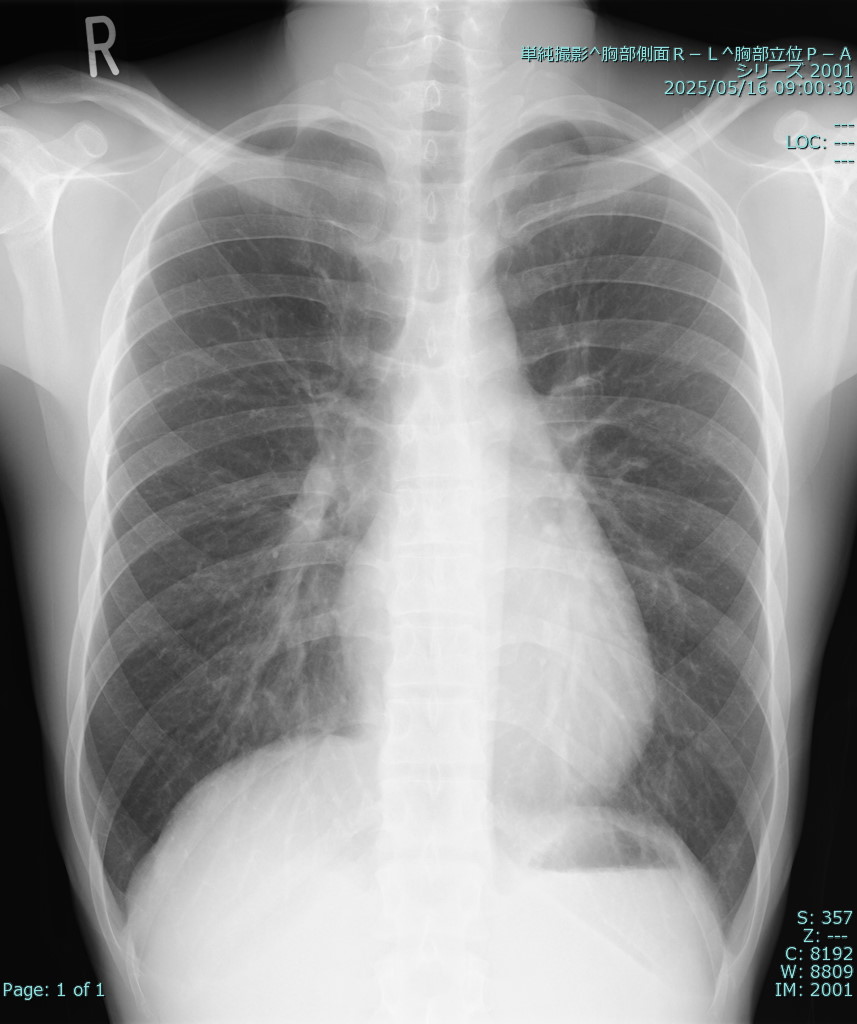

Twenty-six years old male with dyspnea on effort was introduced to our center for percutaneous atrial septal defect (ASD) closure. His heart failure symptom was NYHA class 2m. The auscultation revealed systolic ejection murmur 2/6 at the left second sternal border.

Relevant Test Results Prior to Catheterization

The transthoracic echocardiogram showed a secundum ASD with a dilated right heart, and the transesophageal echocardiogram revealed an ASD without an anterior aortic rim at the 30¡Æ view, measuring 16.4 ¡¿ 11.4 mm. The other rims appeared sufficient, and there was a septal malalignment. Therefore, this case was considered a good indication for percutaneous ASD closure, especially using a GORE ASD Occluder, because of the aortic rim defect.